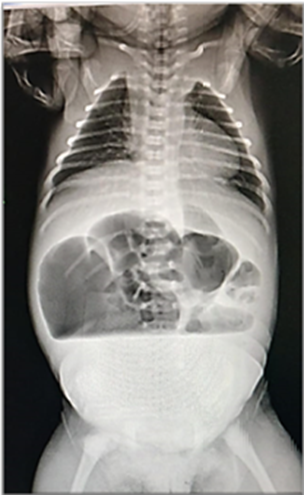

Se realizaron estudios complementarios, entre ellos radiografía de abdomen simple y tomografía axial computarizada de abdomen y pelvis para confirmar el diagnóstico prenatal, donde se evidenció dilatación de asas intestinales en hemiabdomen superior y ausencia de patrón aéreo (Figura 5 - 6). Fue valorado por cirugía pediátrica, quien en vista de los hallazgos decidió llevar a mesa operatoria realizándose laparotomía exploradora. Entre los hallazgos, se describió dilatación intestinal que abarcaba desde el yeyuno hasta parte del íleon distal, de aproximadamente 40 cm, que compartía el mismo mesenterio con el intestino delgado duplicado, lo cual llevó a obstrucción intestinal; el resto del intestino desfuncionalizado, por lo que se corroboró el diagnóstico de duplicación intestinal; además se encontraron bandas de Ladd, las cuales son bandas fibrosas que se asocian a malrotación intestinal y producen obstrucción intestinal a nivel del duodeno (Figura 7).

Figura 5 Radiografía de abdomen simple en suspensión: se evidencia dilatación de asas intestinales en hemiabdomen superior, con evidencia de nivel hidroaéreo, planteándose obstrucción intestinal.